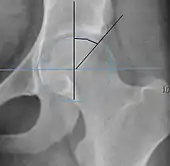

| Crossing ratio | ![]() |

Percentage of acetabular walls crossing. Normal acetabulum is oriented in anteversion. Its value ranges from 15 to 20° in the equatorial plane of the acetabulum and decreases gradually towards the acetabular roof, where normal values range from 0 to 5°. Retroversion of the upper part of the acetabulum has been related with pincer type impingement. In radiography the presence of a "crossover sign" is produced when the posterior wall of the acetabulum crosses the anterior wall before reaching the acetabular roof. It is a sign of acetabular retroversion and it has been linked with overcoverage and pincer impingement. Nevertheless, this sign has been described in 6% of the normal population. Therefore, more important than its presence is the percentage of crossing. | <20%

|